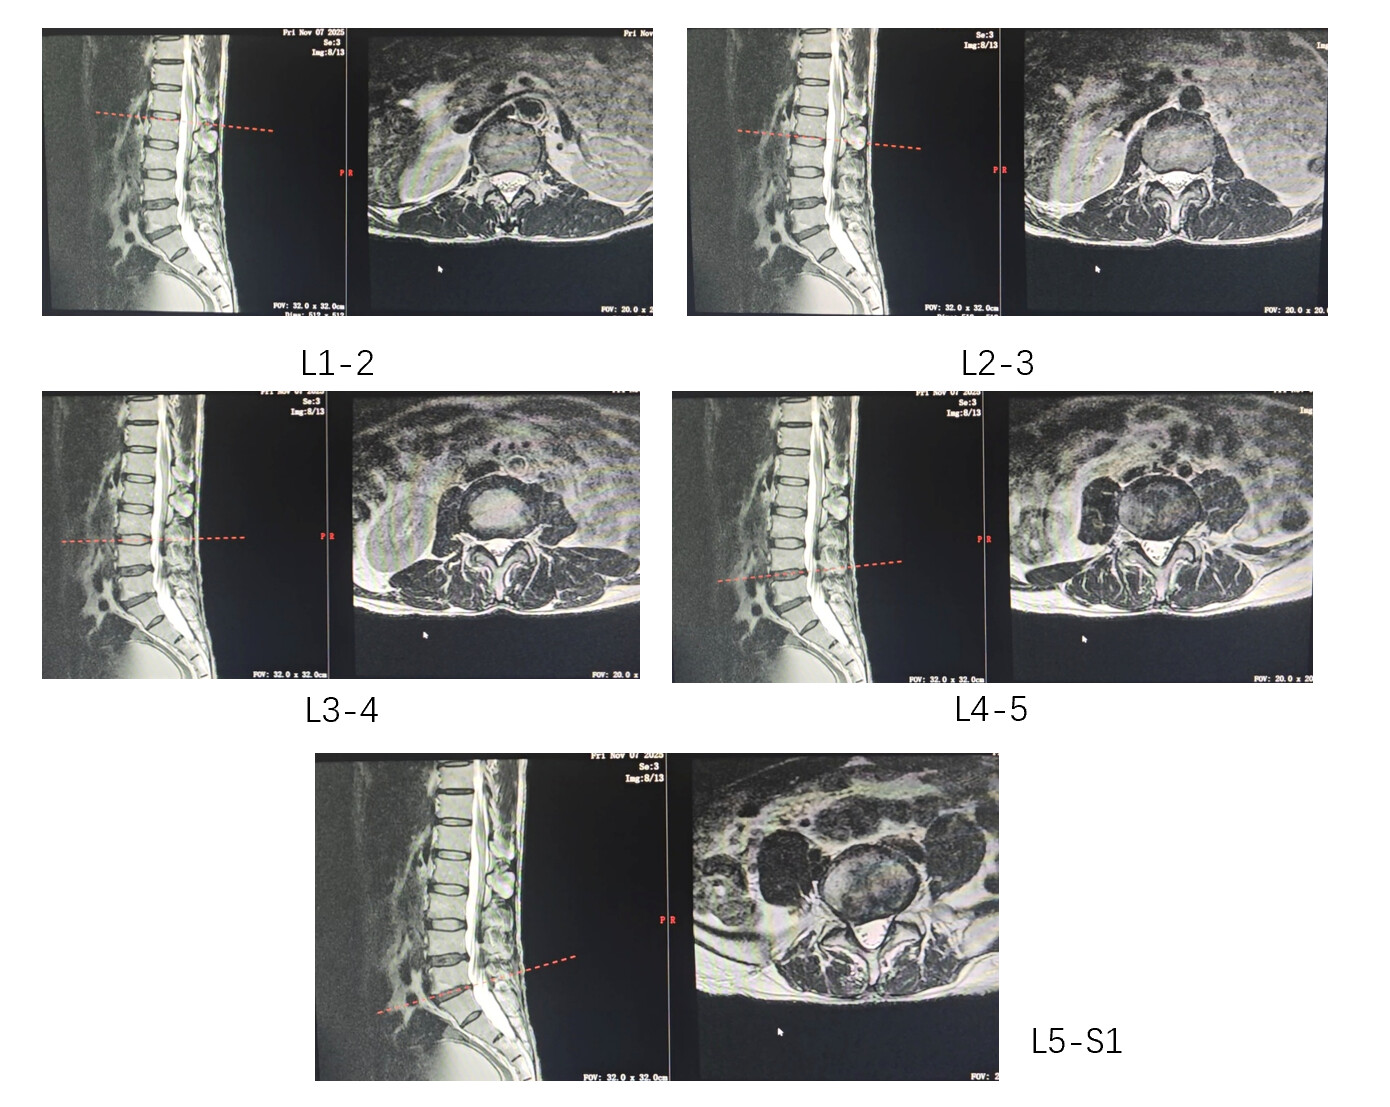

我有一组腰椎核磁的横断面图像,旨在分析五个椎间盘节段(L1/2, L2/3, L3/4, L4/5, L5/S1)。每个节段都包含2-4张DICOM图像。

这是pacs系统显示出来的椎间盘层面